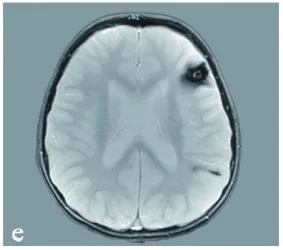

此外还包括左额叶致痫性病灶(图1 e)。图e:显示患儿幕上其他海绵状血管瘤(左额叶及顶叶)。

经抗水肿治疗后,患儿临床状况趋于稳定,神经症状随后改善。MRI显示患儿患有多发性脑海绵状血管畸形。入院时,患儿存在躯干共济失调,几乎无法维持坐姿,不能站立。伴有轻度面瘫和重度右侧偏瘫,同时出现反射亢进和巴宾斯基征阳性(提示中枢神经系统上运动神经元性损害)。